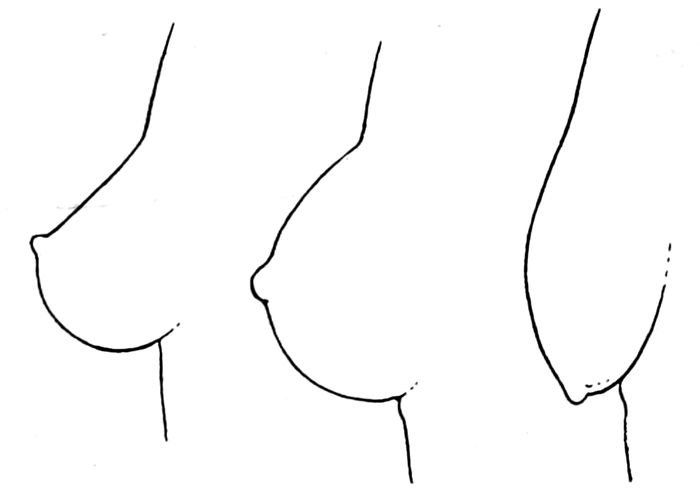

Fig. 11.—The three ages of the breast—virginity, maturity, and senescence. (Witkowski.)

The mammary gland is undeveloped at birth, but, nevertheless

that the functional climax is attained.